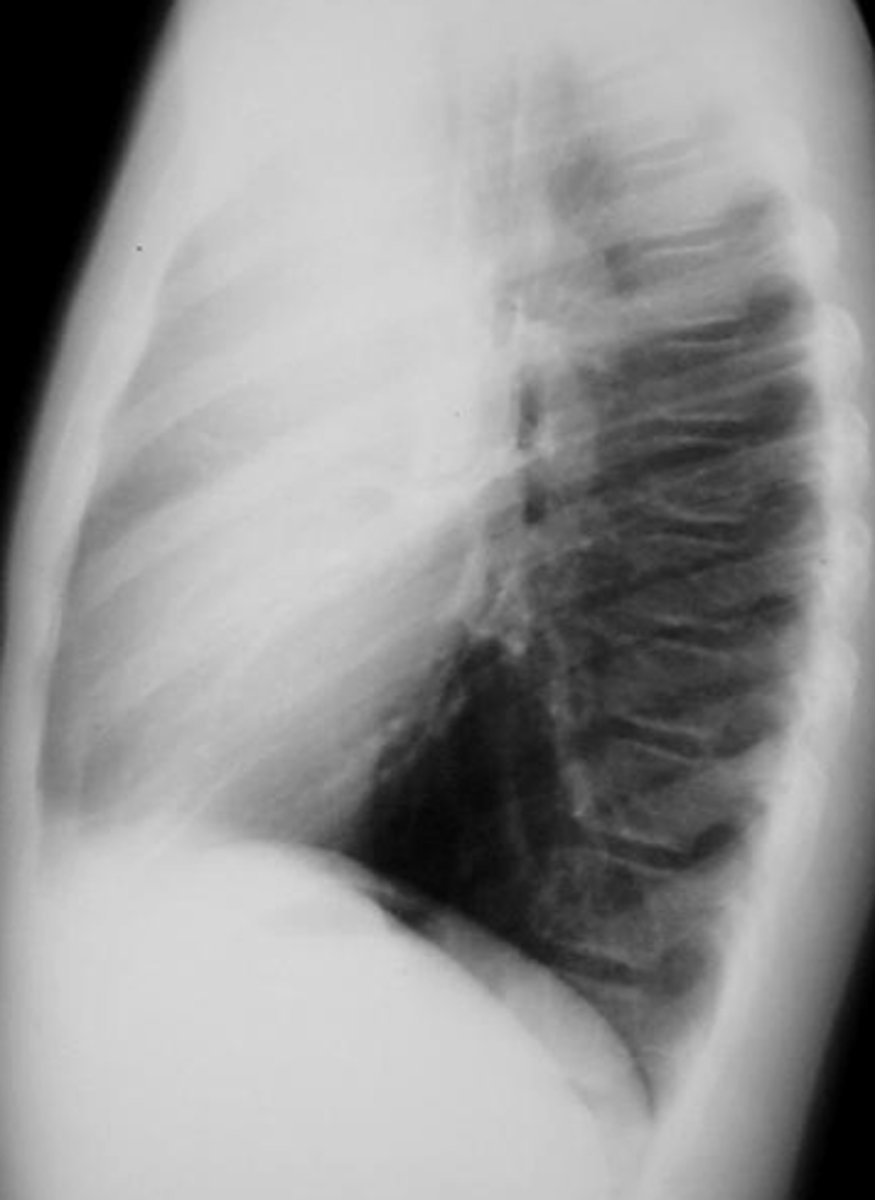

30

New cards

-Congestive heart failure (CHF) - bilateral effusions with cardiomegaly

-Pneumonia - 40% have a small effusion

-Pancreatitis - L sided effusion

-Cirrhosis - R sided effusion

-Malignancy - massive effusion

Causes of pleural effusion

<p>Causes of pleural effusion</p>

31

Pleural effusion

-fluid build up is pushing the mediastinum laterally which causes the t spine to be more visible

-can use lateral decubitus position to confirm presence of effusion/fluid

Dx

<p>Dx</p>